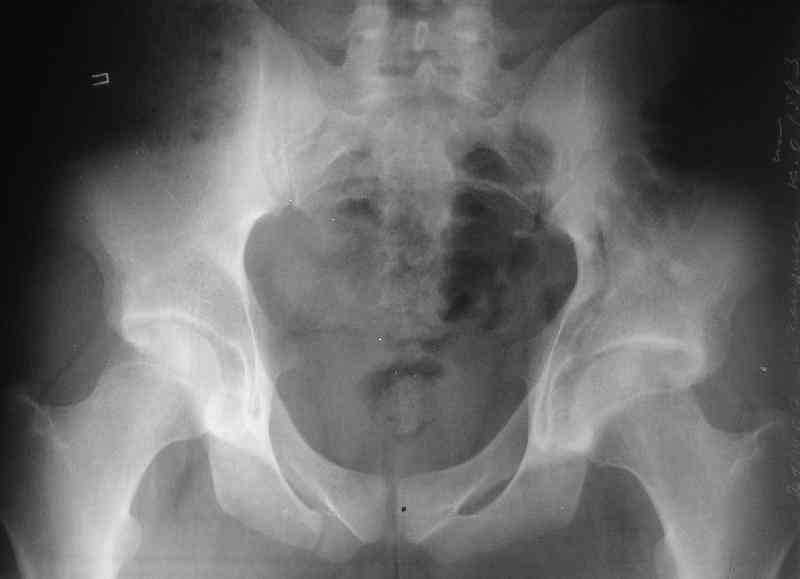

Нелеченный перелом вертлужной впадины

Мужчина 33 лет получил травму в шахте (придавило вагонеткой) 6 недель назад. Изолированное повреждение вертлужной впадины.

В местной больнице отлежал несколько недель на вытяжении. После выписки амбулатрный травматолог направил в институт. На сегодня, похоже, уже имеется неправиильное сращение. См. картинки.

Вопрос - что делать сейчас? Оставить как есть или идти на открытое восстановление? Если последнее, то какой доступ, репозиционные манипуляции и фиксацию тут можно посоветовать?Заранее спасибо.

Dear all,A male 23 y.o. injured 6 weeks ago - mine trauma, impacted by a carriage. Isolated injury of the acetabulum. At the initial hosptial was on bed traction some weeks. After discharge visited anotheк orthopaedic surgeon who referred him to our unit. To date looks like a malunion. Images attached. The question is about what to do now - either leave it as is or perform open reduction? If the latter what approach, reduction manoeuvres and fixation would you advice? Thx in advance!

What is your indication for surgical management? What kind of fracture do you think it is? It looks like a transverse type although it has been a couple of years since I looked at an acetabular fracture.

My concern would be that the risk of leaving it malreduced is very high. It appears to be primarily a gap rather than a step in the articular surface. Do you have any CT views that show an articular step?

The last two images from the 3-D CT scan certainly makes the fracture look worse than the plan radiographs.